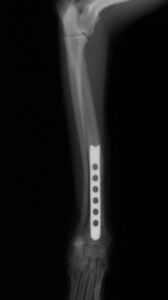

その後、1か月普通に生活していました。レントゲンを撮ったところ、骨は十分に増生していたので、心配ないと判断しプレートを取りました。プレート除去前

プレート除去後

プレート除去後は何の問題もなく生活しています。うまくいきました。